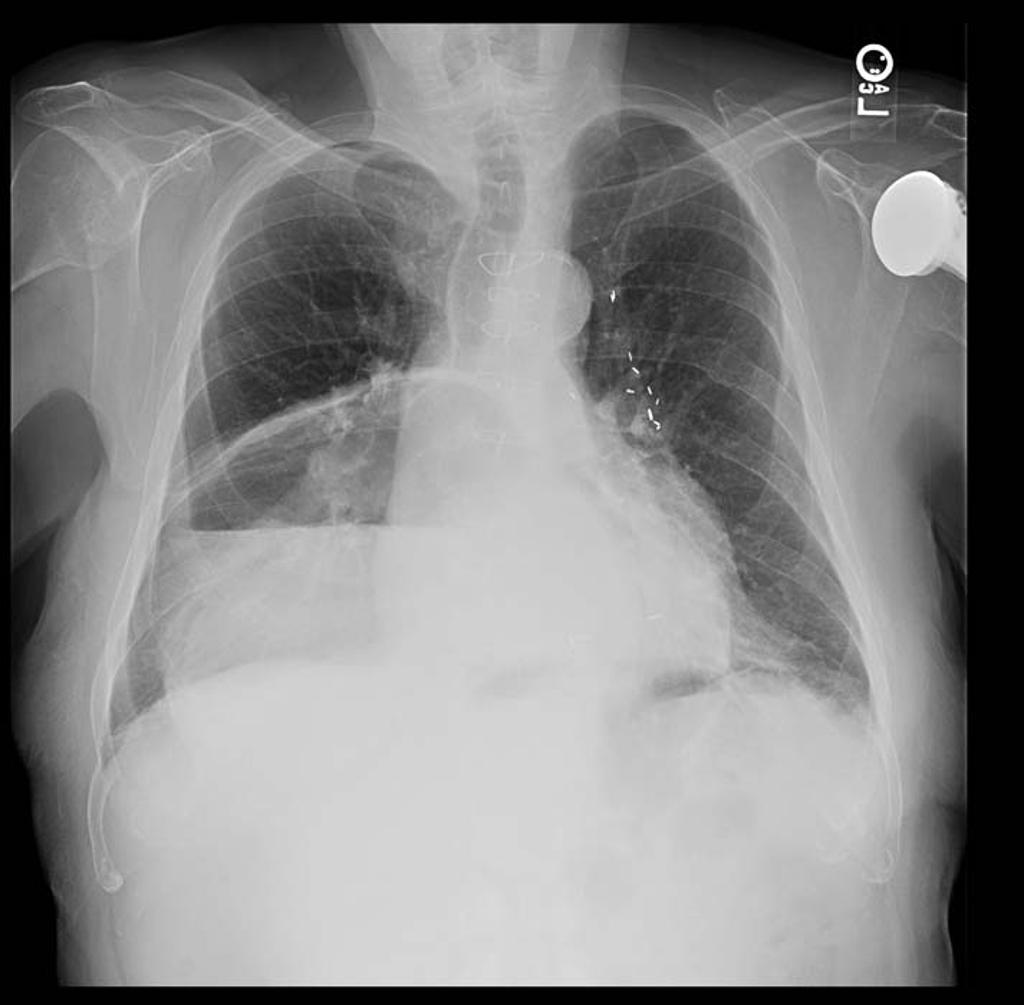

Image hydro -aerique

en niveau de estomac dans cas hernie hiatale par

roulement avec volvulus gastrique du partie hernie

du corp gastrique . Cliche pulmonaire de face |